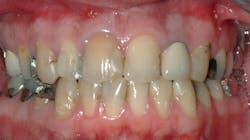

However, when blended with the clinical experiences of long-term CR clinicians, this information should be useful for you and your patients. The example in Figures 1 and 2 shows a patient who was not told by the practitioner that his previous restorations would eventually need to be replaced. This is the situation with many patients.